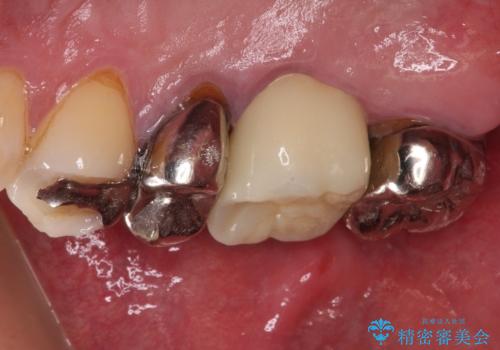

- ものが挟まるとのことで来院された患者様です。

一度は治療せずに放置していましたが、1年後のメインテナンスの際に悪化していることが分かったことから、補綴治療を行うこととしました。

神経を抜いてある歯はむし歯が進行しても痛みを感じることがないため、気がついたときには著しくむし歯が進行している可能性があります。

早めの対応とすることで、抜歯を回避できることはもちろん、外科処置などの本来必要のない処置を行わずに対処することができました。